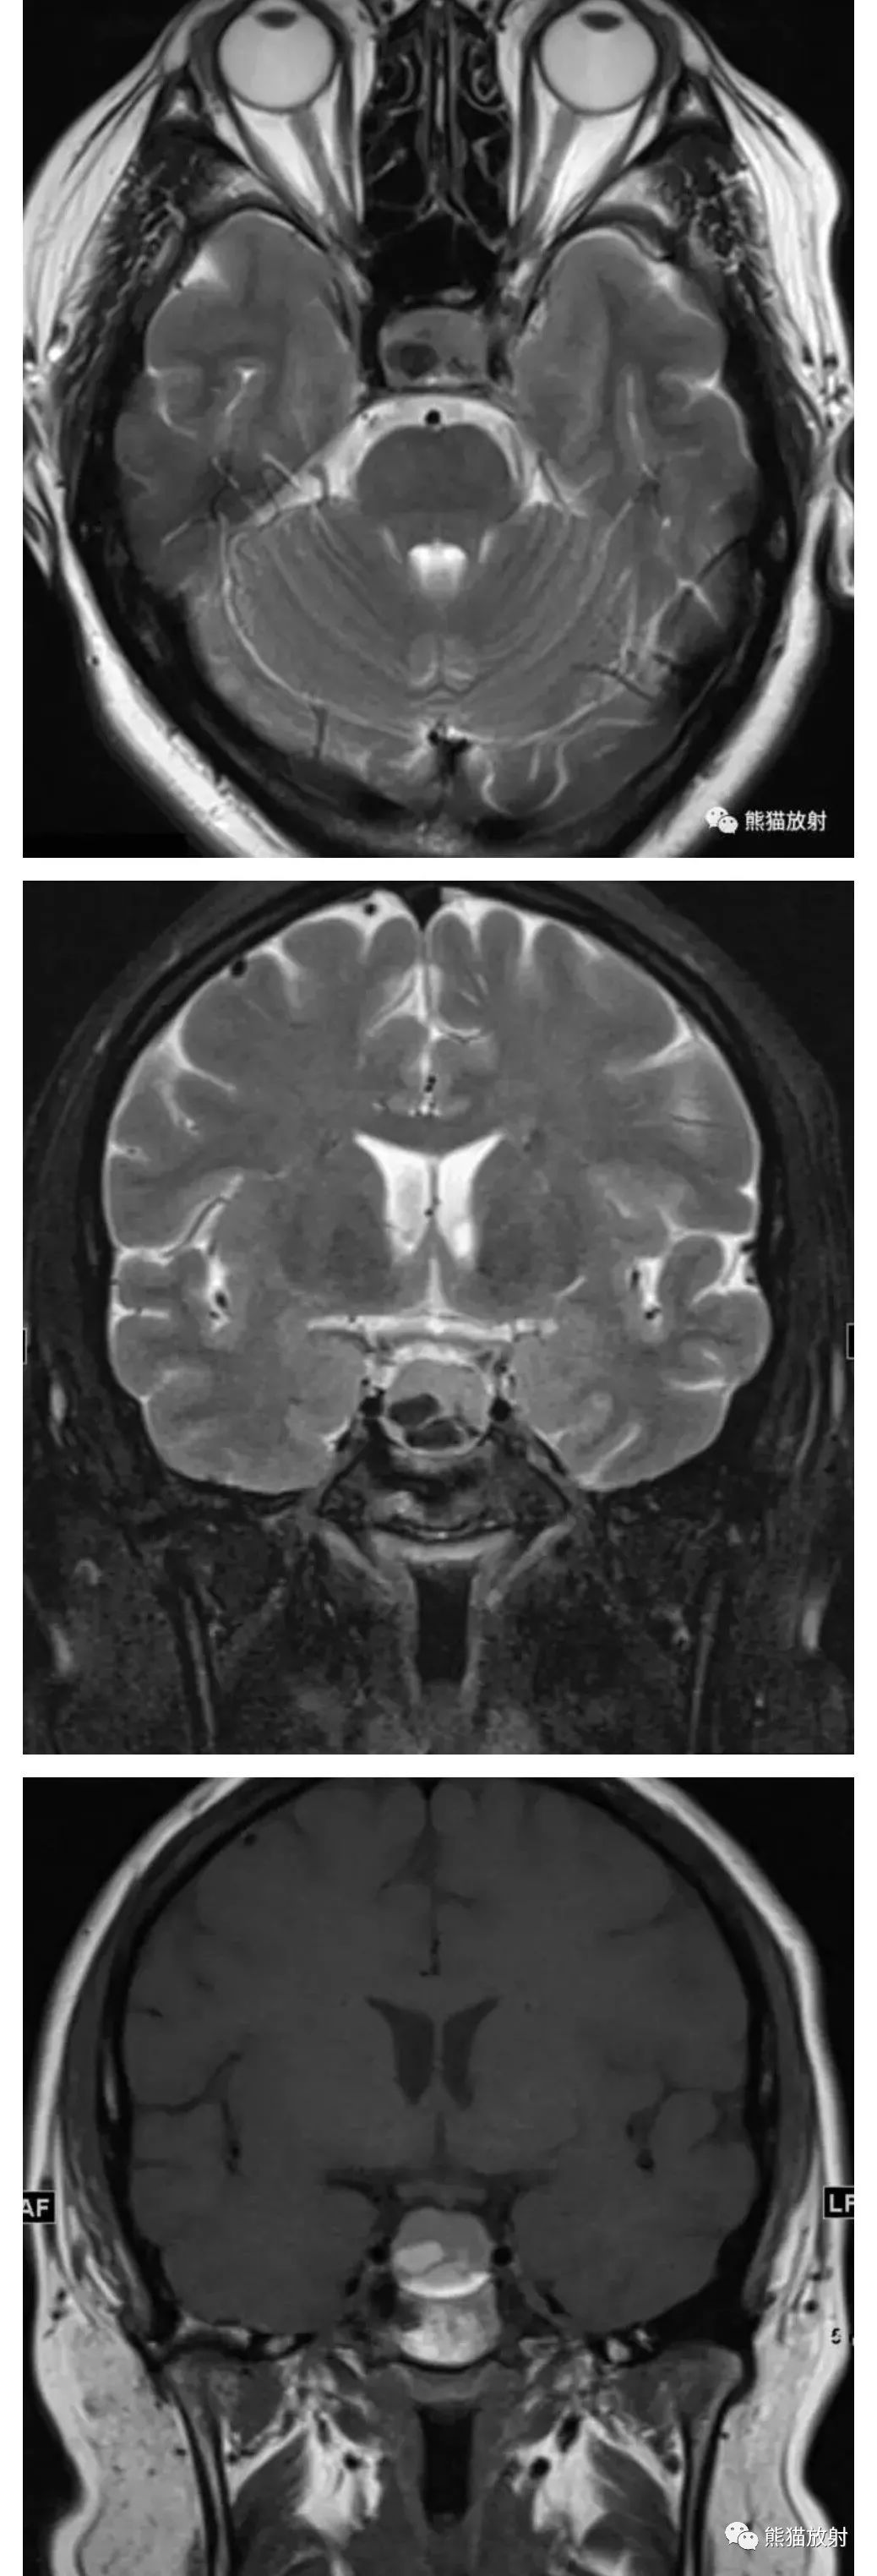

鞍区t1高信号病变之[rathke囊肿]丨小打卡读片精选(27)

图片尺寸1038x3048

图片尺寸1000x3000